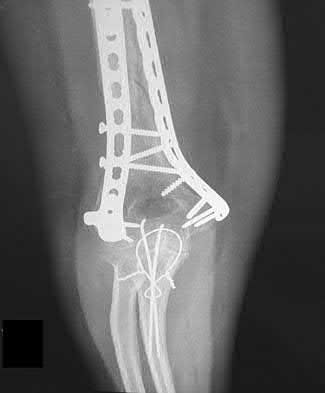

1. # A 32-year-old male sustains the injury shown in Figure A and undergoes treatment as shown in Figure B. Following placement of this implant, what is the best technique to confirm it is not too proud proximally?

The safe zone for tibial nail placement as seen on radiographs is just medial to the lateral tibial spine on the anteroposterior radiograph and immediately adjacent and anterior to the articular surface as visualized on the lateral radiograph.

Tornetta et al specifically located the safe zone for nail entry in a study using fresh frozen cadaver knees. The authors found that the safe zone for nail placement is located 9.1+/-5 millimeters lateral to the midline of the plateau and three millimeters lateral to the center of the tibial tubercle. The width of the safe zone averaged 22.9 millimeters and was as narrow as 12.6 millimeters.

The starting point of the of the nail can be best viewed on the lateral knee radiograph, an example of which is shown in Illustration A. Illustration B shows the "sweet spot" for nail insertion as defined by Tornetta.